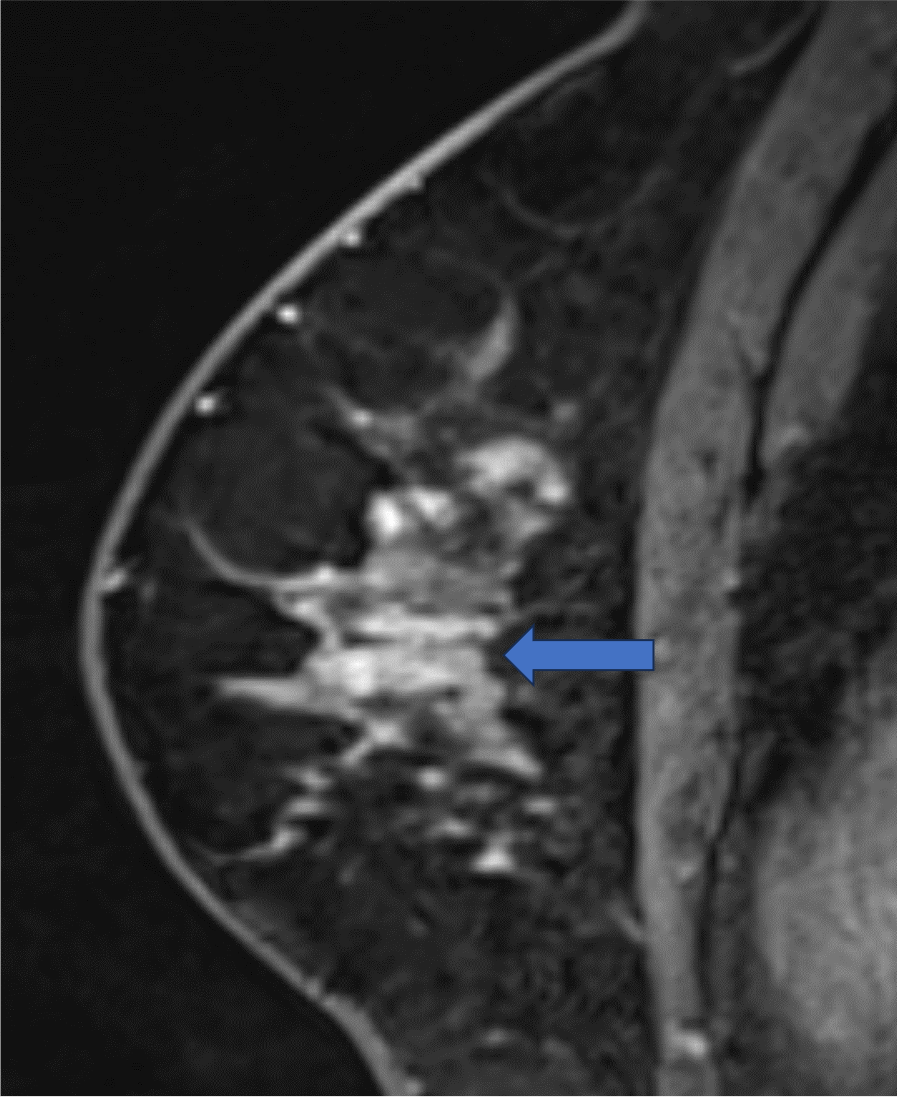

5. Ultrafast DCE 造影剤投与約20秒後、23秒後、26秒後

BPEが目立たないため、左乳房内側の病変が容易に同定できる

ultrafast MRI 造影剤投与

約23秒後

約26秒後